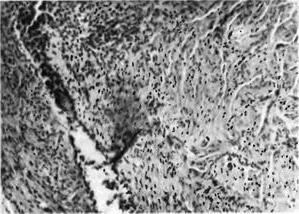

![]() Рис. 3. Нагноєння в зоні ендометріозу. |

Навколо вогнищ ендометріозу завжди розвивається запальна реакція, ступінь вираженості якої може бути досить різноманітною. Вогнища ендометріозу можуть піддаватися нагноєння (рис. 3).

Частіше інших локалізацій це спостерігається при ендометріозі яєчників (кістозній формі ураження) і маткових труб. Нагноєння ендометріозу ускладнює перебіг захворювання і може викликати утруднення в діагностиці.